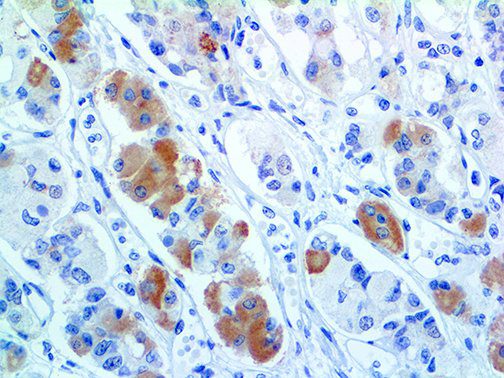

The first cytokines released are interleukin 1β (IL-1β) and tumor necrosis factor-α (TNF-α), which attract a variety of circulating white blood cells (WBCs) to the infection site, including neutrophils, monocytes, macrophages, and natural killer (NK) cells. This response, along with the antipathogenic chemicals released by these cells (i.e., complement), comprise the innate immune response. These cells directly attack the invading pathogen and also release additional cytokines, chief among them interleukin-1 and 6 (IL-6). IL-6 is essential for invoking the adaptive immune response, which calls T-cells, B-cells, and T helper (Th) cells to the infection site. IL-6 also stimulates further recruitment, proliferation and activation of macrophages.

It is the ICU physician who is most likely to witness one of the deadliest manifestations of the abnormal immunological response, the cytokine storm syndrome (CSS). This response is also referred to by some as the cytokine release syndrome (CRS). CSS is characterized by continuous activation and expansion of macrophage and lymphocyte populations, which secrete large amounts of cytokines, causing the cytokine storm. This massive cytokine release is akin to hemophagocytic lymphohistiocytosis (HLH) disease, a syndrome characterized by initial unchecked and persistent activation of cytotoxic T lymphocytes and NK cells.